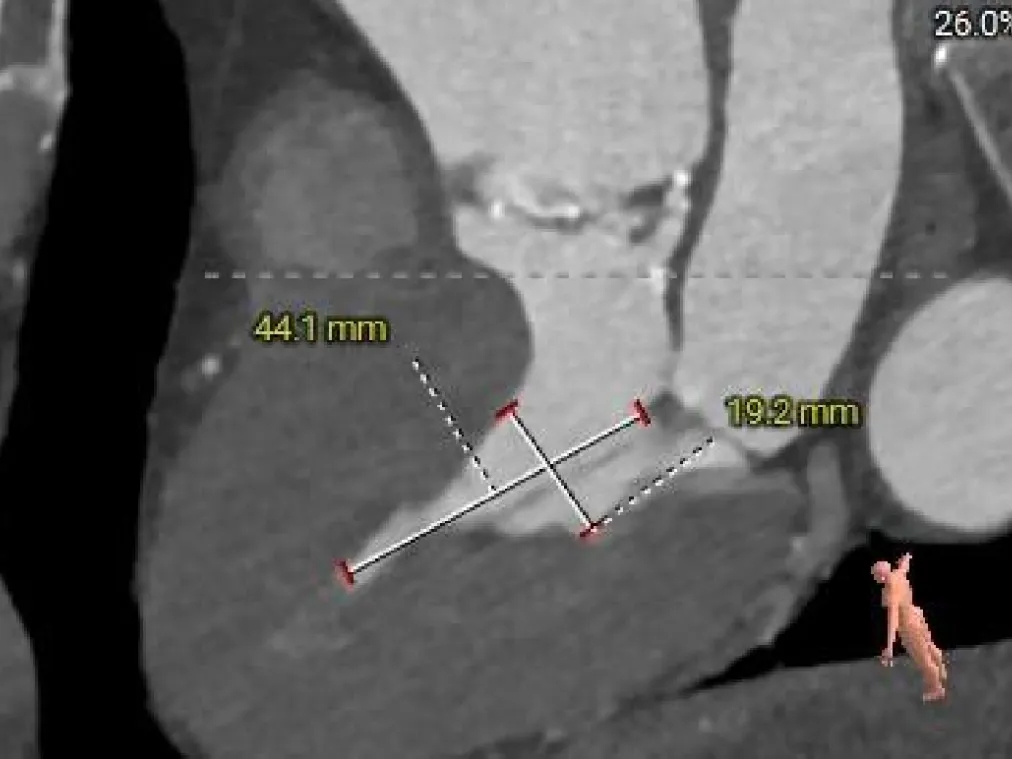

术前CT分析

TYPE-0型二叶瓣(纵列式),重度钙化,钙化分布不均匀,延伸至流出道可见,瓣叶明显增厚;

瓣环径约为24.0mm,流出道偏收口型,心室壁增厚,收缩期小心室;

左冠开口高度约为23.8mm,右冠开口高度约为27.0mm;

瓣环水平夹角47度,非横位心,升主动脉明显扩张;

外周入路走形轻度迂曲,左右股动脉直径尚可,主动脉弓部、腹主动脉处见少量钙化附着;

左侧下肢动脉入路最小平均内径6.7mm,右侧下肢动脉入路最小平均内径6.8mm。

瓣上结构测量

瓣上2mm

23.4mm

瓣上4mm

25.5mm

瓣上6mm

25.3mm

瓣上8mm

25mm

瓣上10mm

26.6mm

瓣上12mm

26.8mm

外周入路评估